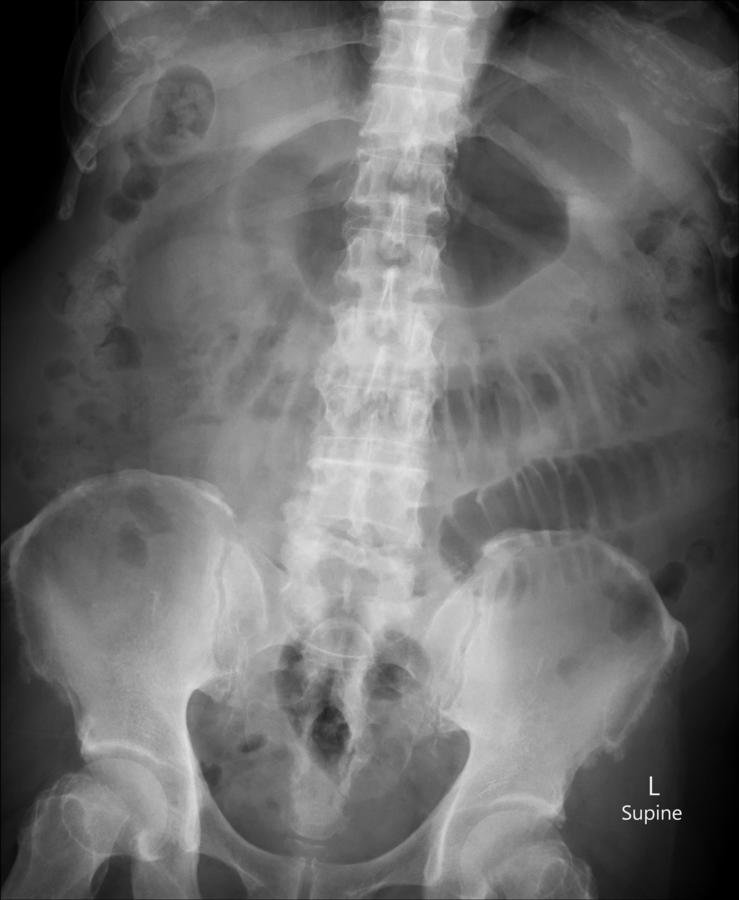

History :  A 65-year-old female with abdominal pain and vomitting

What is the positive finding in the plain abdominal radiograph?

Answer : B. Small bowel dilatation

Plain abdominal radiograph shows :

• Several dilated loops of gas filled bowel with diameter more than 3 cm

• Valvulae conniventes are visible - confirming this is small bowel

-> Small bowel obstruction